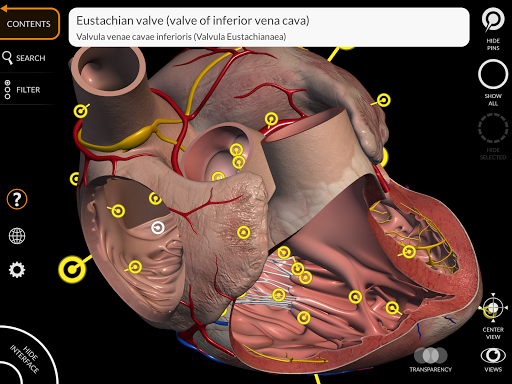

"Anatomy 3D Atlas" дозволяє легко та інтерактивно вивчати анатомію людини.

Завдяки простому та інтуїтивно зрозумілому інтерфейсу можна спостерігати кожну анатомічну структуру під будь-яким кутом.

Анатомічні 3D-моделі особливо деталізовані та мають текстури з роздільною здатністю до 4k.

Поділ за регіонами та попередньо визначені види полегшують спостереження та вивчення окремих частин або груп систем і зв’язків між різними органами.

• Серцево-судинна система

• Обертайте та збільшуйте кожну модель Тривимірний простір

• Можливість приховування або ізоляції однієї чи кількох вибраних моделей

• Функція закладок для збереження користувальницьких переглядів

• Вибравши модель або шпильку, з’явиться відповідний анатомічний термін